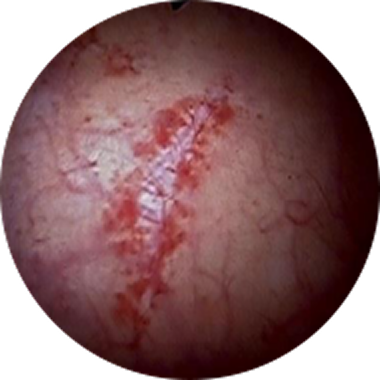

궤양 병변

간질성 방광염

궤양 병변Check